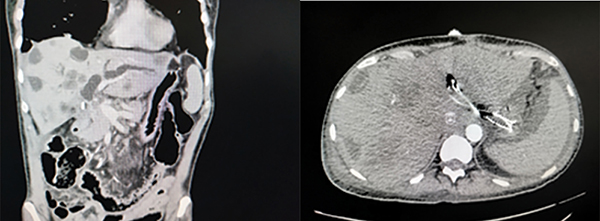

Az EUS-BD módszereinek ismertetése (1. ábra)

B: EUH-vezérelt antegrád stentelés, C: EUS-CDS, D: EUH-vezérelt cholecystadrenázs, E: EDGE, F: EUS-HGS (forrás: ESGE 2022 guideline) (34)

EUS-HGS (EUH-vezérelt hepaticogastrostomia)

Az eljárás során a gyomor felől a máj bal lebenyének S2 (könnyebb manipuláció, de súlyosabb szövődmények) vagy S3 epeútjait (nehezebb manipuláció, de biztonságosabb) (14) drenáljuk speciális öntáguló fémstenttel (SEMS) (2. ábra), vagy ritkábban plasztikstenttel (3. ábra), amelynek a májban levő része fedetlen, míg a máj és a gyomor között fedett. Az eljárás során a kiválasztott epeutat egy 19G-s EUS-tűvel pungáljuk, majd epeaspirációt végzünk, az eperendszer kontrasztos feltöltése során 0,035-es vagy 0,025-es vezetődrótot helyezünk be. Ezután fistulaképzést végzünk (6 Fr cystotom ± ballon), és végül a speciális fémstenttel kialakítjuk a drenázst (15). Az eljárás technikai sikeraránya 96,6–97,7%, míg a klinikai sikeressége 88,1–91,1%, de a nemkívánatos események aránya magasabb (12–17,5%), mint az EUS-CDS-nél tapasztalt 12,2% (16, 17). Ezen sikerességi arány eléréséhez hosszú tanulási görbe vezet (>4 év) (17). Az ESGE ajánlása szerint EUS-HGS csak inoperábilis malignus hilaris epeúti szűkületben javasolt tág bal eperendszer esetén, nagy volumenű centrumokban (18).

EUS-CDS (EUH-vezérelt choledochoduodenostomia)

Az eljárás olyan esetekben alkalmazható, amelyeknél a bulbus az eszköz számára biztonságosan elérhető, és az epe elvezetése megoldott a vékonybél distalis irányába (GEA, átjárható duodenum). Ezen eljárás alkalmával a bulbusból „hosszú úton” pungáljuk a közös epevezetéket a lézió felett és a hilus alatt ideálisan 3-4 cm-rel. Itt alkalmazhatunk lumenösszetartó fémstentet (LAMS), illetve vezetődrót mentén 6 Fr-es cystotommal átégetve a nyombél és az epeút falát 6 cm-es fedett SEMS-et (4. ábra). Alkalmazható randevútechnika ezen pozícióból is, de ekkor „rövid úton” a papilla irányába állunk az eszközzel. Az EUS-CDS-t vizsgáló 2024-es metaanalízis (845 beteg) a technikai és klinikai sikerességet 96%-osnak találta. A nemkívánatos események aránya 12% volt. Itt a 8×8 mm-es LAMS jobb volt a nemkívánatos események terén, mint a 6×8 mm-es (19).